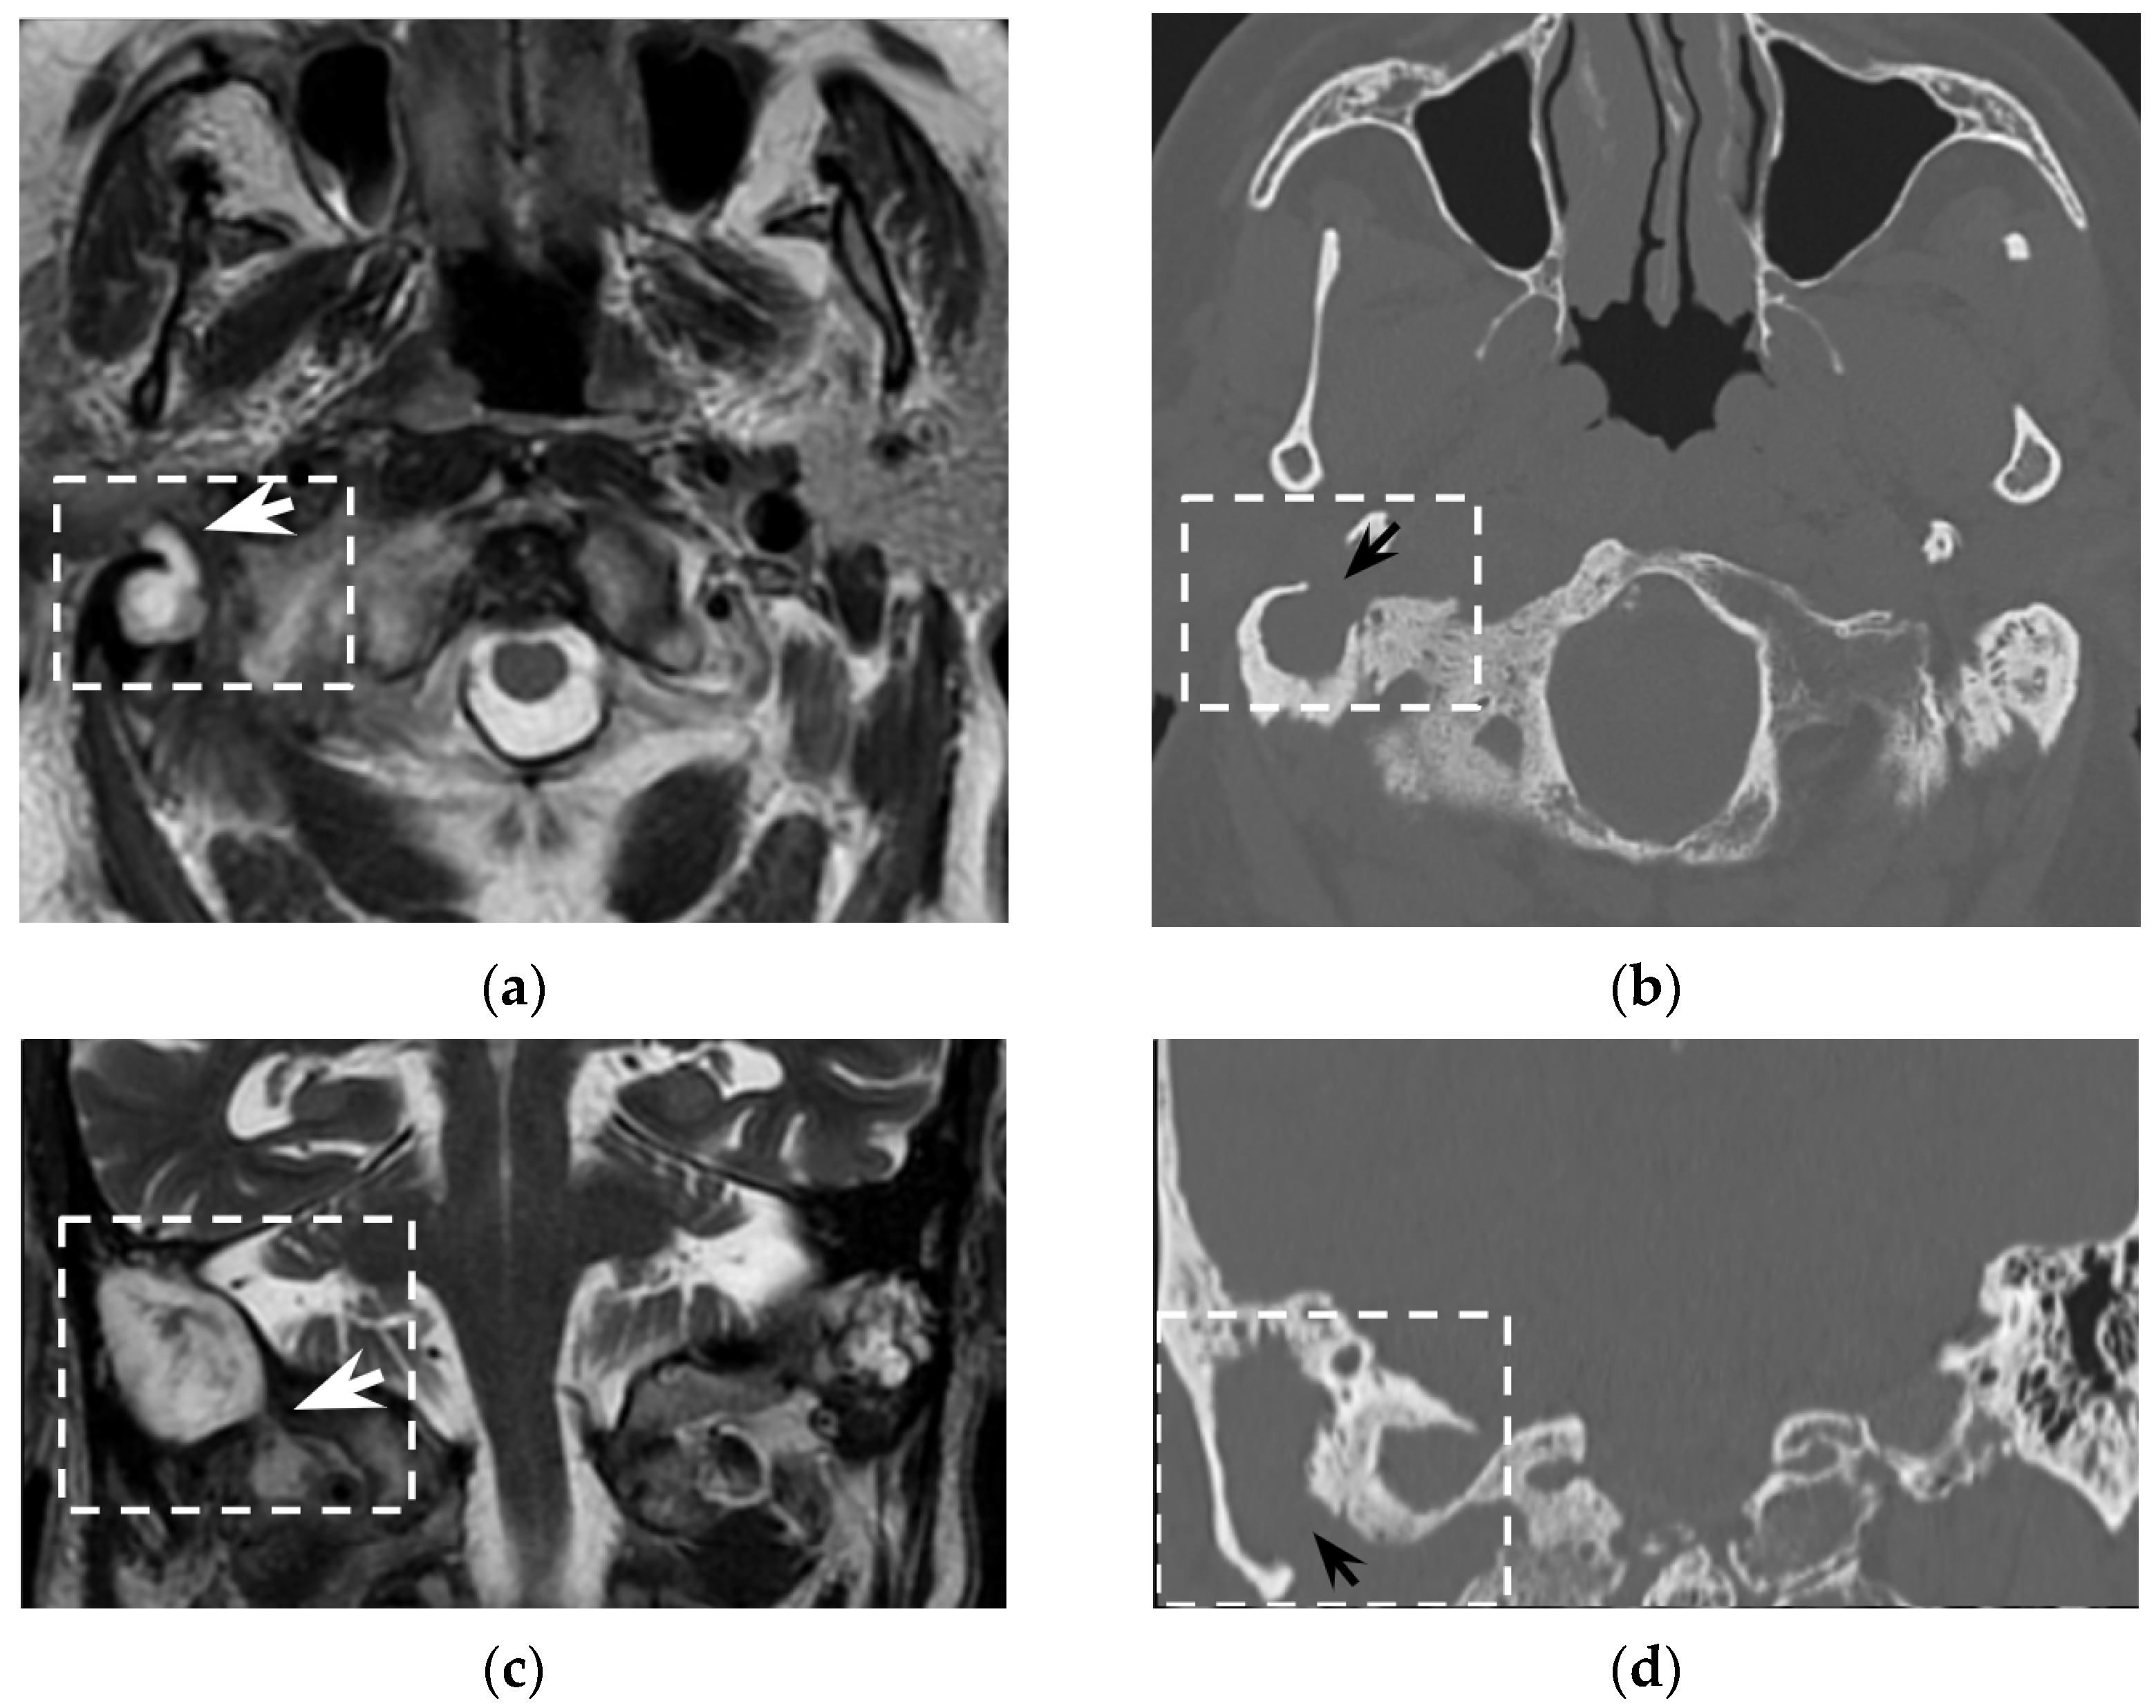

In the clinical suspicion of a Bezold’s abscess, temporal bone CT and contrast enhanced neck CT are the gold standard [7] for defining two main diagnostic aspects: (1) the site of mastoid bone erosion in the context of a mastoiditis and (2) the anatomical boundaries of the neck suppurative collection. Temporal bone CT typically shows signs of mastoiditis, such as opacification of the mastoid cells and erosion of the mastoid bone trabeculae. High resolution (slice thickness < 1 mm), coronal plane reconstructions, high frequency bone kernel and bone window are suggested to enable the detection of small bone interruptions at the mastoid tip, generally at the digastric groove (Figure 4).

However, despite its crucial pathogenic role for the suppurative path, bone defects in the mastoid tip have been precisely outlined only in around half of all literature reports (51/97 patients, 53%). Indeed, in 7/97 patients (7%) the mastoid tip was considered intact, revealing that the diagnosis of Bezold’s abscess can be achieved even without overt bone erosion, especially in younger children (3/7 patients were younger than 5 years old). The incomplete pneumatization of mastoid cells before the age of five is well known and is supposed to hinder the diffusion of the suppurative process across the thickened mastoid bone wall. Before the age of five, more destructive infectious processes or emissary vein bone canals likely allow Bezold’s abscess occurrence [8]. A recent case of a woman affected by Goldenhar syndrome with an unremarkable mastoid bone (Figure 5) highlighted those atypical origins of Bezold’s abscess that should be accurately investigated in syndromic patients [15].

Contrast-enhanced neck CT aims at demonstrating and precisely defining the anatomical limits of the neck abscess that appears as a low-attenuation collection with typical rim enhancement (Figure 4) and surrounding soft tissue oedema. Neck CT should be reconstructed with 2–3 mm thick slices and a soft tissue kernel and window. The suppurative collection is usually located under the sternocleidomastoid muscle, in the posterior-cervical or perivertebral spaces, but extensions into the retropharyngeal space [30,51], parapharyngeal space [30,42,45,53], or even into the thorax [24,26,46,54] have been described, coherently with neck fascial anatomy and least resistance pathways.

Figure 4. Eighty-seven-year-old man with history of external mycotic otitis. T2w MRI in axial (a) and coronal (c) planes show abnormal right mastoid (dotted rectangle) filled with hyperintense material that spreads into the neck (white arrows). Axial (b) and coronal (d) bone CT images show opacified right mastoid, absence of bone trabeculae, and a wide defect (black arrows) at the mastoid tip. Images were consistent with an infected cholesteatoma eroding the mastoid tip and spreading into the neck. The finding was confirmed at surgery.